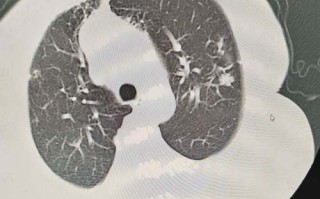

新生儿健康护理 最新 剖腹产新生儿肺部感染风险高,如何有效预防与科学护理? 为什么剖腹产会增加新生儿肺部感染的风险?这主要是因为剖腹产新生儿错过了在自然分娩过程中经历的一场“肺部洗礼”,自然分娩是一个“循序渐进”的过程,对新生儿肺部成熟至关重要:激素的调动:分娩过程中,母体和... 99ANYc3cd6 2026-02-09 1 #剖腹产新生儿肺部感染预防 #剖腹产宝宝肺部护理方法 #降低剖腹产新生儿肺部感染风险